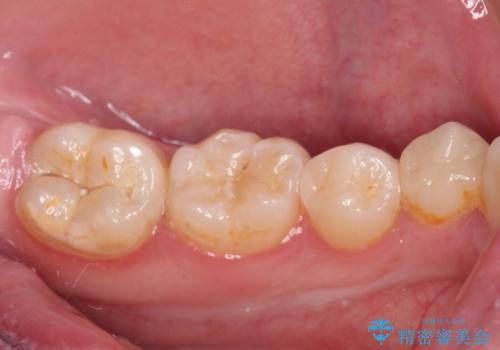

食べ物がはさまりにくくなり、冷たいものがしみる症状もなくなり、大変満足していただきました。

放置しても良いことはないため、もし詰め物がかけてしまったのに気が付いたら早めに歯科医院を受診されるのをお勧めいたします。